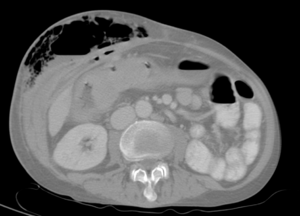

| Abdominal CT with right colocutaneous fistula and associated subcutaneous emphysema. | |

يتم وضع التشخيص الأكيد عن طريق التصوير الطبقي المحوري CT.Scan.